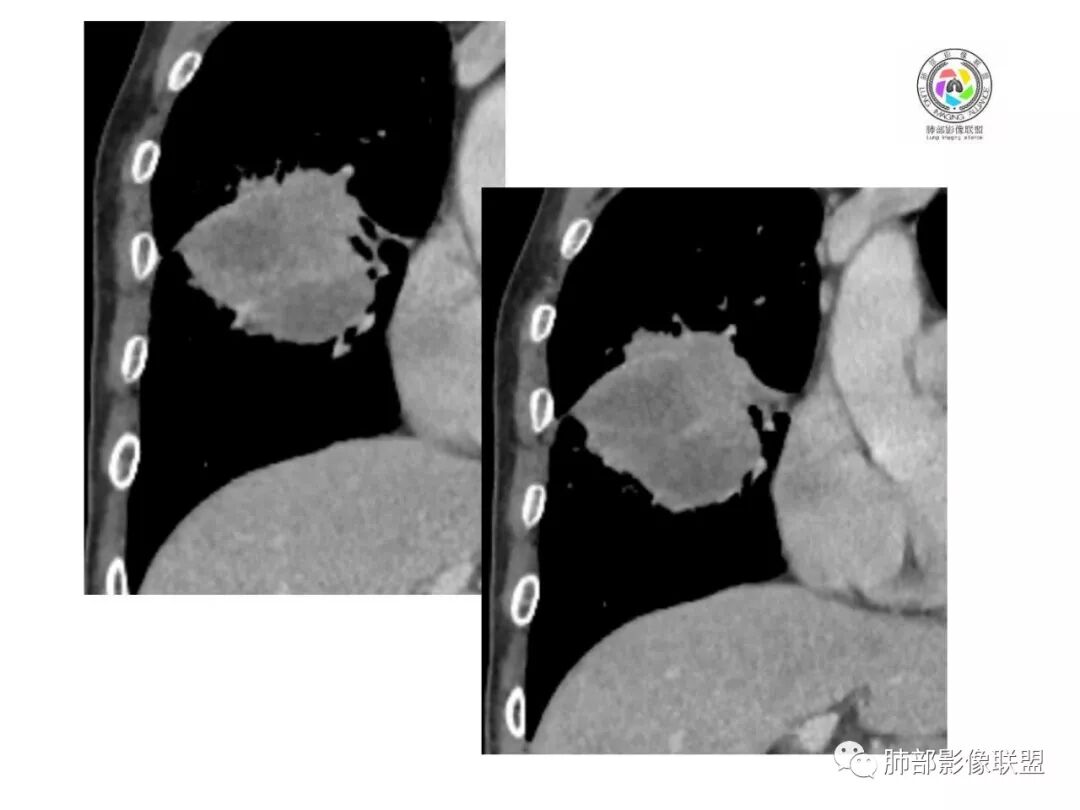

1.具有肉瘤的特性:肿瘤体积一般较大,直径约大于5cm,边缘清楚、光整,由于肿瘤生长迅速,可见大片坏死,坏死边界清楚;常见支气管推移。

2.具有癌些特性:如分叶、短毛刺、空洞,但是钙化及胸膜凹陷征少见,病灶往往是直接侵犯胸膜,可以远处转移,肺门及纵隔淋巴结可明显肿大;

3.强化方式:增强后病灶以环状强化为主,病灶周边多以癌组织为主,血供丰富,病灶中心区则以肉瘤成分为主,血供较差,易出现粘液样变性、坏死、出血,坏死边界清楚,所以增强CT对PSC与普通型肺癌有一定的鉴别价值。

1.本病例结合病理结果及影像综合分析,应该符合肉瘤样癌,上皮成分是腺癌为主;肿块的边缘毛刺、分叶及周围癌型淋巴管炎征象有符合腺癌的影像表现之处。

2.肿块巨大局部边缘膨隆、光整,坏死较彻底;明显跨叶生长(途经发育不全叶间裂或肺门,注意患者没有胸水),支气管阻塞伴推移等,这些更符合肉瘤的特性。

3.坏死区边界较清楚(皮囊样),环形强化明显,病灶内血管穿行等,都不符合我们常见的鳞癌。